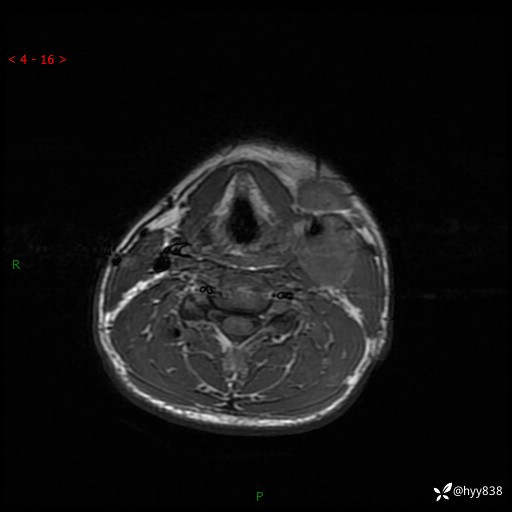

年轻小伙,发现左侧颈部肿物3年余,逐渐增大---结果公布~

现病史:患者约3年前因感冒发现左侧颈部长一肿物,约半个鸡蛋大小,无明显疼痛及其他不适,一直未行特殊处理。3个月前发现左侧颈部肿物变大,随后至当地市第二人民医院耳鼻喉科行左侧颈部彩超示:左侧颈部囊实混合性包块;喉部MPR示:左侧胸锁乳突肌内前方占位,累及左侧喉旁间隙,建议增强扫描。建议手术治疗。患者考虑。随后至我院肿瘤科就诊,行细胞学穿刺示:考虑血管源性肿瘤可能,建议进一步检查。建议至我院口腔科就诊,行颌面部MRI示:左侧颌下腺后方团状异常信号灶,建议增强。建议手术治疗。为求进一步治疗,门诊以“左侧颈部肿物”收入院。 起病以来,患者神志清、精神良好,饮食睡眠良好,大小便正常,体重未见明显变化。

颈部MRI平扫+增强